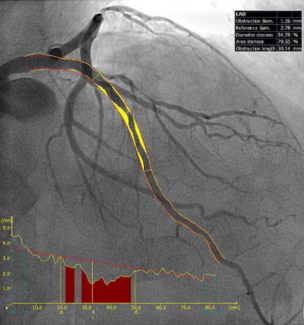

Although visual assessment of stenosis severity is routinely used to guide coronary revascularization, there are concerns about its accuracy, especially in women, who present a higher variability in coronary anatomy and ischemic heart disease.